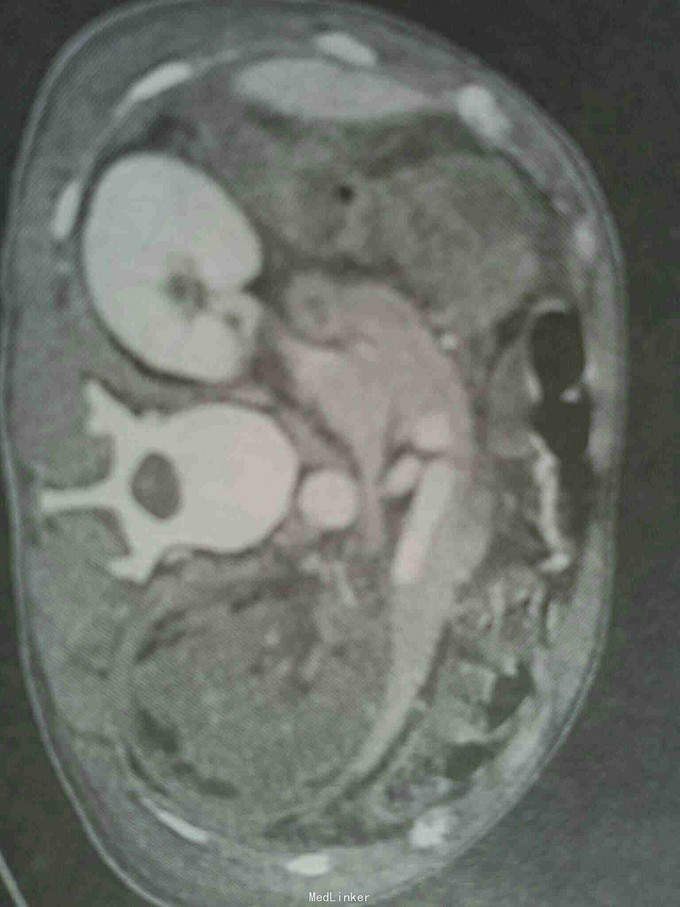

车祸后腹痛伴肉眼血尿半天。 病史:一天前患者走路时被摩托车从腰部撞伤,外伤后有短暂的昏迷。伤后感腹痛,疼痛为持续性钝痛移动体位时疼痛感加剧,无恶心呕吐,同时出现小便呈全程红色,无尿痛,未见明显的血凝块。

体温脉搏血压基本正常,腹部饱满全腹压痛左腰肌左侧上腹压痛明显,无反跳痛,左肾区叩压痛,右肾区外形正常无扣压痛,双侧输尿管走行区无压痛耻骨上膀胱区无隆起,无触痛。 ct检查结果提示肾挫裂伤,肾周血肿。

左側肾挫裂伤 左側肾周血肿 治疗:1.绝对卧床4周,休息3个月 2.住院期间严密监測患者各项生命休征变化。 3.出院后定期门诊复查。